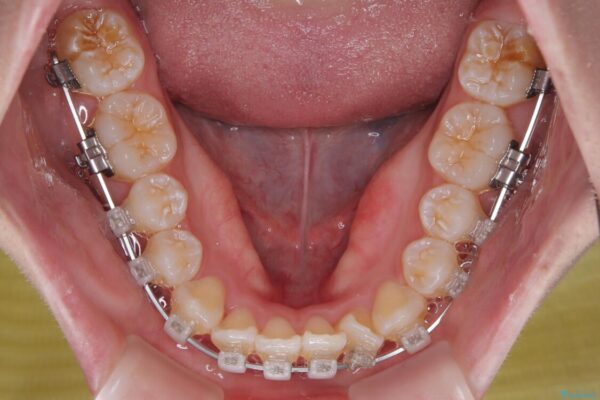

治療途中

• 【モニター】前歯のデコボコをスッキリ解消!目立ちにくいワイヤー矯正でスピーディに治療完了 治療途中画像

目立ちにくさと費用のバランスを考慮し、プラスチックブラケット+メタルワイヤーを採用。日常生活でも装置の存在感を気にせずお過ごしいただけます。